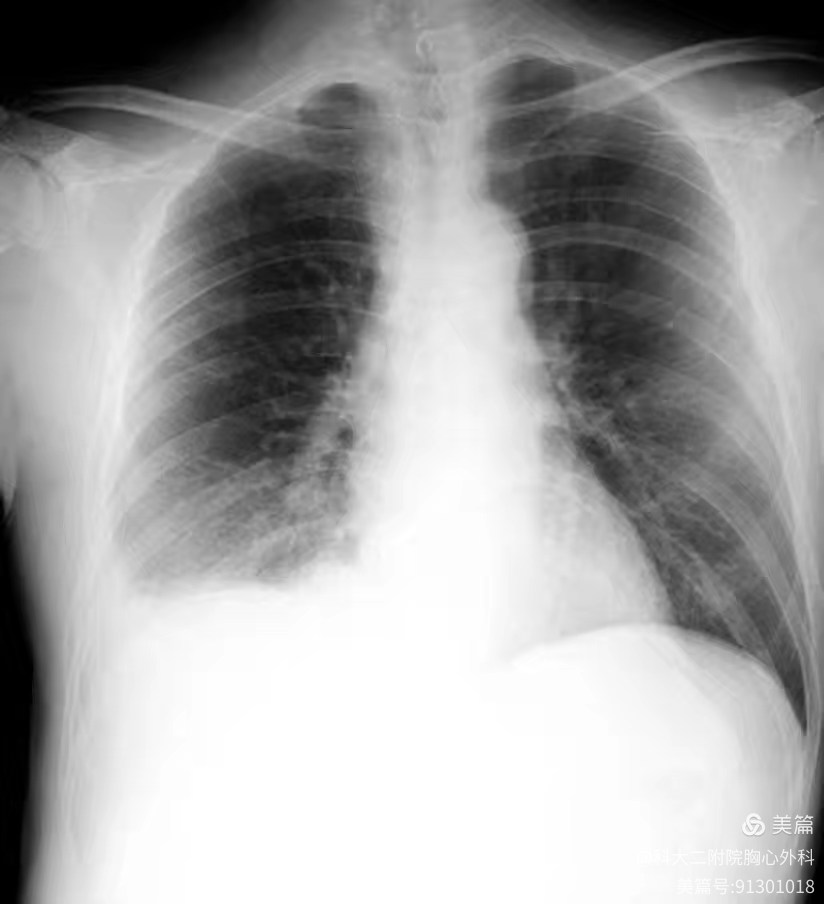

前不久的一次聚餐中,李叔叔在饮用鱼汤后突发剧烈呕吐,右背部出现强烈的疼痛感。李叔叔被紧急送往河南科技大学第二附属医院胸心外科就诊,胸部 X 光片捕捉到了胸腔积液的异常阴影,随后的 CT 检查更清晰地揭示了危机源头——食管壁异常增厚、周围气体影密布,消化道造影显示有穿孔,李叔叔最终被确诊为 食管破裂。